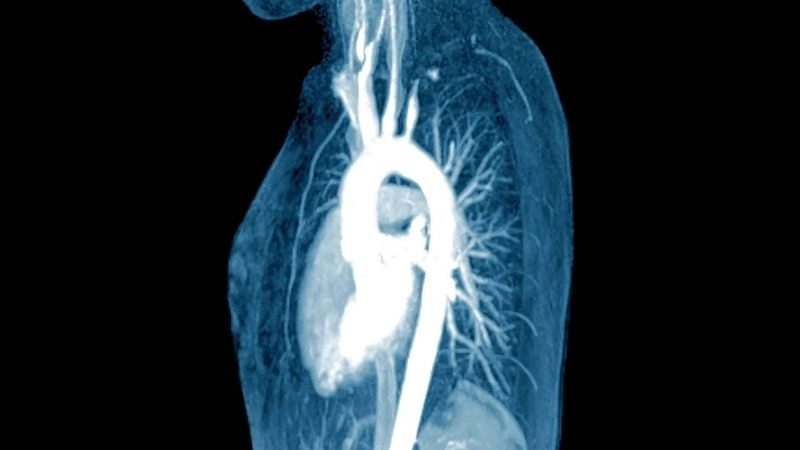

Takayasu's arteritis diagnosis with imaging tests

Images visual examples of Takayasu's arteritis

Takayasu's arteritis is a rare chronic inflammatory disease affecting large blood vessels, particularly the aorta and its branches, leading to narrowing and reduced blood flow.